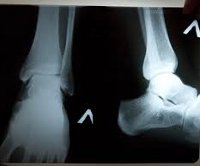

Radiography of the ankle joint.

Рентгенография голеностопного сустава

Рентгенография голеностопного сустава в травматологии показана при подозрении на перелом в течение одного, двух или трех лет, перелом пяточной кости и таранной кости, перелом голеностопного сустава и остеомиелит. В ортопедии назначают исследование при приобретенных и врожденных деформациях, дистрофических дегенеративных заболеваниях (остеоартрозе) различной этиологии. В ревматологии этот метод используется для лечения артрита и подагры, в то время как в онкологии предполагается, что на костную ткань влияет первичная или метастатическая опухоль.